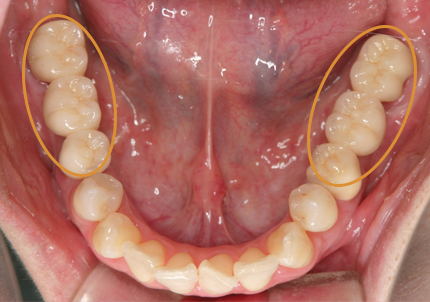

1.初診時口腔内(2007年6月30日)

8.初診より現在に至る

強い歯ぎしり、くいしばりで奥歯の歯牙破折、深い虫歯で保存不可能となり全顎治療となる。

↑ 2007年6月30日(初診)

↑ 2025年9月9日

治療後は経過良好